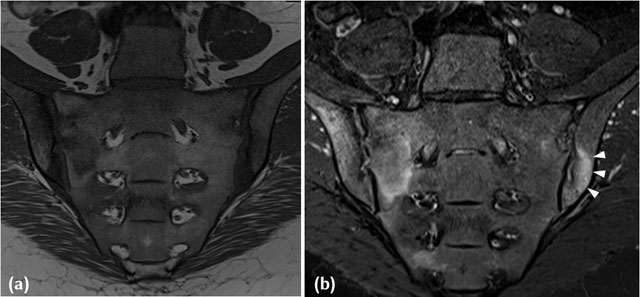

Figure 2

(a) T1-W Mid-coronal MRI in a 38-year-old HLAB27 positive, Female patient who presented with inflammatory back pain and buttock pain. Areas of joint space widening with iliac sided erosions and adjacent marrow low signal intensity are noted in keeping with active inflammatory lesions. (b) Corresponding STIR image in a 38-year-old HLAB27 positive, Female patient who presented with inflammatory back pain and buttock pain, demonstrates extensive high signal intensity (white arrowheads) in the adjacent subchondral region and marrow in keeping with inflammation associated with an active erosion.